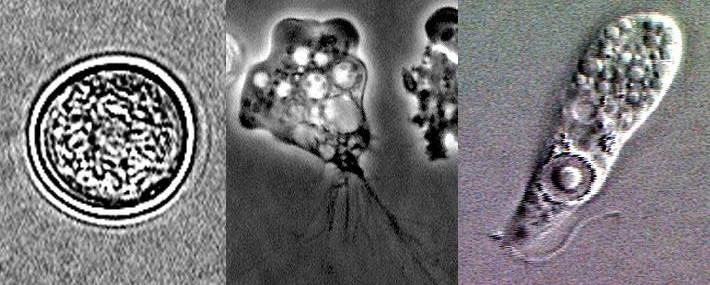

Неглерия Фоулера (смотрите фото) является простейшим патогенным микроорганизмом с примитивным строением. Он может паразитировать в организме человека и существовать вне организма носителя. Относится амеба к роду одноклеточных эукариотов.

Размножается Неглерия Фоулера в теплых водоемах. Подходящей температурой для того, чтобы амеба мозгоед размножалась, является температура приблизительно 35 С. Для сохранения численности мозгоед приобрел способность избыточно размножаться при помощи деления. В благоприятных условиях у паразита появляются жгутики, помогающие ему передвигаться.

Неглерия Фоулера отличается уникальным жизненным циклом. В неблагоприятных условиях амеба мозгоед стает округлой формы и покрывается довольно плотной оболочкой. Последняя носит название циста. В данном состоянии Неглерия Фоулера может пребывать длительный период. Только когда исчезает угроза, амеба возвращается в активное состояние. Данный жизненный цикл обеспечивает высокую живучесть микроорганизму. Неглерия не погибает под воздействием низких либо высоких температур.